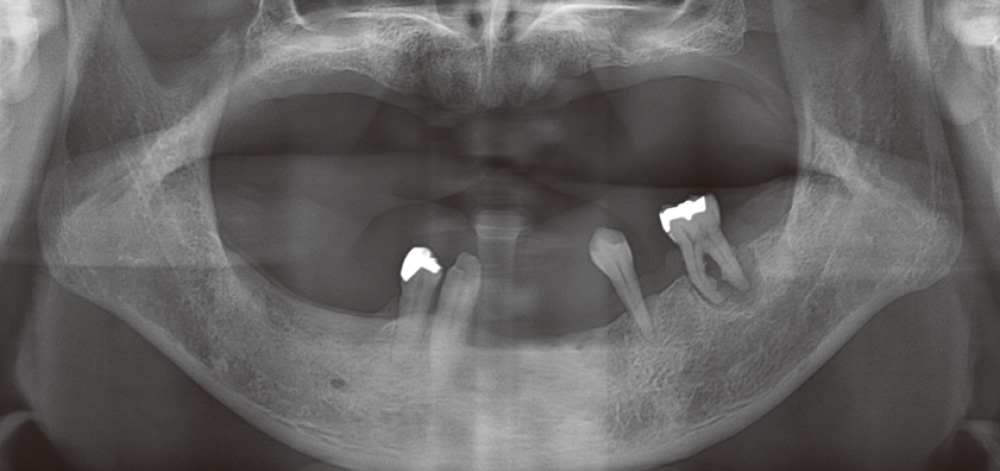

67歳男性、43の垂直的骨欠損への対応

基本的に痛くなってからしか来ない患者の典型的症例(図3)。残存している下顎右側犬歯と第一小臼歯臼歯間のサイナストラクト発症により来院。側枝からの感染による歯髄壊死も考えられたため、ガッタパーチャを挿入後に、デンタル撮影にて部位特定。歯周病急性症状改善後、歯周ポケット測定を行うと舌側中央に8mmのポケットを確認した(図4)。

図3 初診時パノラマX線写真。36分岐部や43・44部に骨吸収が確認できる。 -